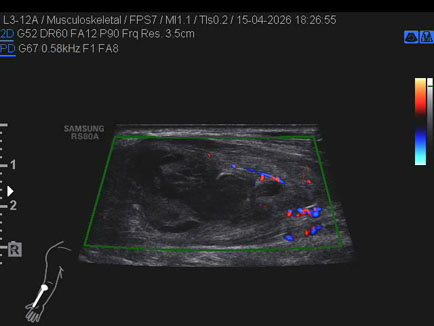

Data inserimento: 17/04/2026

Ecografia del: 15/04/2026

Strumento: Samsung

Sonda: Lineare

Commento all'esame: ematoma post trauma da sforzo del lungo supinatore dx in anziano sottoposto a terapia con i NAO.

Conclusioni: ematoma del muscolo lungo supinatore destro (hematoma of the right supinator longus muscle).